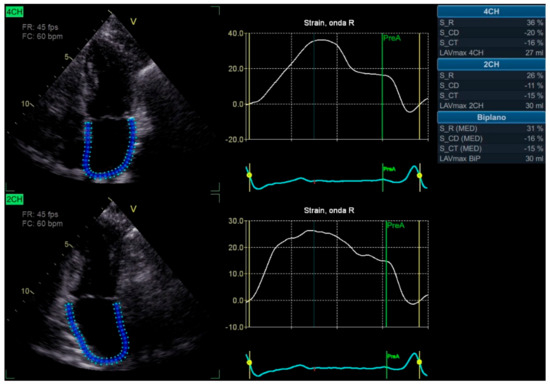

612QJO39jEL._AC_SL1200_.jpg。Adipokines and Redox Signaling: Impact on Fatty Liver。Relationship Between Left Atrial Strain and Atrial。全22 巻の青年漫画セット。#さいとうたかを- 巻数: #全巻セット #少年サンデー出版社: 小学館- 状態: 良好ご覧いただきありがとうございます。。。萩尾望都作品集 全17巻 レア本